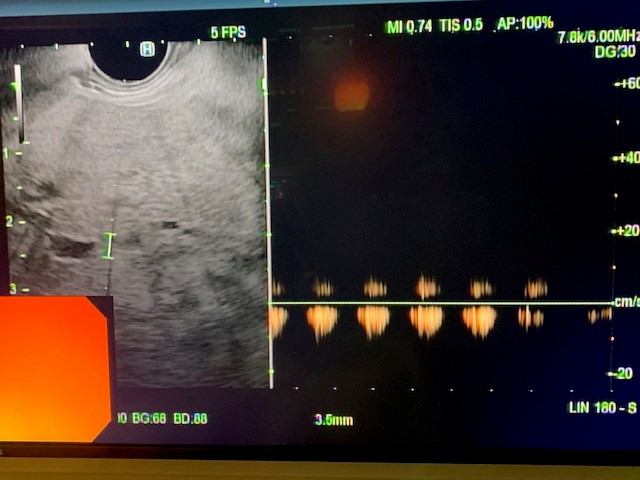

Under general anesthesia, esophagogastroduodenoscopy (EGD) was done using a gastroscope (Olympus America) and there were no esophageal or gastric varices noted. Next, EUS linear array echoendoscope (Olympus America) was passed into the esophagus and advanced into the stomach. The ultrasound image of the liver showed diffuse fatty infiltration. We performed portal pressure gradient using a 25-gauge Cook Echo Tip Insight needle (Cook Endoscopy, Winston Salem, NC). Pulse wave Doppler was used to confirm the middle hepatic vein. From the stomach through the left lobe of the liver, the middle hepatic vein was accessed, and three pressure measurements were taken using digital manometry (Figure 2). The average of 3 measurements from the middle hepatic vein was 17 mmHg. Pulse wave Doppler was used to confirm the left portal vein (Figure 3). Then from the stomach we measured the portal vein pressure by accessing the left portal vein and the average of three measurements was 18 mmHg (Figure 4), giving her a PPG of 1 mmHg. Using Doppler, we ensured there was no bleeding when the needle was withdrawn from both veins (Figure 5 and 6). After the portal pressure gradient measurement, liver core biopsies were done using a 19-gauge Boston Scientific FNB needle (Boston Scientific Marlborough, MA). From the stomach, the left liver lobe was biopsied with the use of EUS to confirm the absence of blood vessels in the needle’s trajectory. One pass and three actuations using the wet heparin technique was performed. The right liver lobe was biopsied from the duodenum and similar methodology was done using the same needle and technique. No bleeding was noted. Both core liver biopsies were sent in formalin to the pathology department for further evaluation.

Figure 1: Pulse wave Doppler of the middle hepatic vein.

Figure 2: Middle hepatic vein needle with manometry to obtain hepatic vein pressure accessed via transgastric, transhepatic approach.